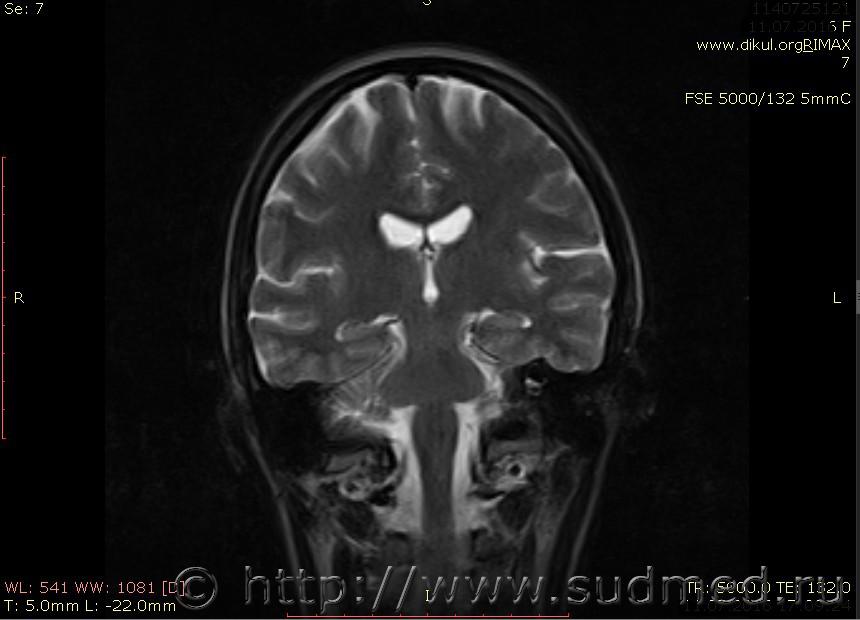

МРТ головного мозга показало: МР-данных за наличие очаговых изменений в веществе головного мозга на момент исследования не выявлено. МР-признаки нарушения соотношения в атланто-осевом суставе. Определяется ассиметрия положения зубовидного отростка С2 относительно боковых масс С1(справа 6,5; слева 4 мм.)

Сама по себе эта информация даёт основания подозревать вывих первого шейного позвонка, но однозначно не свидетельствует о наличии вывиха. Нужно смотреть на снимках наличие реакции со стороны мягких тканей, в т.ч. связочного аппарата, нужно анализировать особенности неврологической патологии, её динамику и проч.

Запрошен электронный вариант снимков из учреждения, где делалось МРТ. Т.к. с самого снимка делать копии не получается,очень мелкие кадры. Завтра попробую вставить в сообщение. (Но СМЭ снимок не смотрел, смотрел только мед.карту, в которой находилось описание МРТ).

Посмотрите пожалуйста снимки, надеюсь на них видны позвонки С1,С2?

Прошу прощения, попробую снова прикрепить файлы. Данные учреждения и пациента убраны.